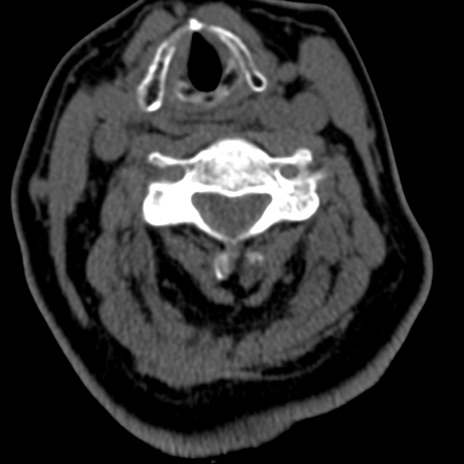

症例50 頚椎CT(横断像)

頚椎CT